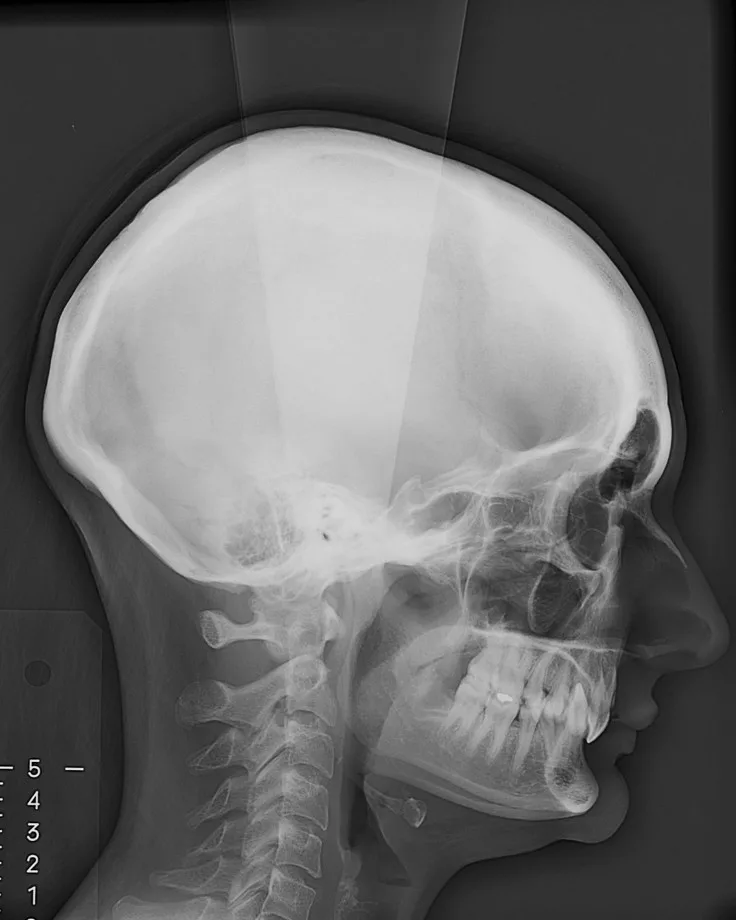

Parmi les examens radiographiques nécessaires, les radiographies de profil et de face correctement orientées et contenant l’ensemble de la tête (sommet du crâne inclus) sont particulièrement importantes. Ces radiographies correctement effectuées permettent d’établir une véritable cartographie du squelette du patient et en conséquence de comprendre sa malformation. Cette analyse cartographique du squelette a pour nom « céphalométrie ». De nombreux types d’analyses céphalométriques existent et sont utilisées selon les pays et universités. Parmi elles, l’analyse céphalométrique architecturale et structurale de Jean Delaire tient une place particulière.

L’Analyse Céphalométrique architecturale et structurale de Jean Delaire

L’analyse céphalométrique architecturale crânio-faciale de Jean Delaire, à la différence des autres méthodes d’analyse qui sont principalement basées sur des moyennes statistiques définissant ce qui est « normal » et ce qui est « anormal » (c’est à dire pathologique) est basée sur la notion d’équilibre ou de déséquilibre architectural du squelette crânio-facial propre à chaque individu en tenant compte des principaux appareils anatomiques à son contact et des principales fonctions qui interfèrent avec lui. « A l’état d’équilibre, tous les éléments de l’extrémité céphalique ; squelette et tissus mous sont et fonctionnent en parfait équilibre mutuel ».

Pour chaque individu, l’analyse architecturale crânio-faciale de Jean Delaire permet de déterminer « l’équilibre » squelettique idéal qui lui est propre c’est-à-dire « sa normalité » et de constater, s’il existe, l’état de «déséquilibre » dans lequel il se trouve, c’est-à-dire l’état « pathologique » dans lequel il se trouve en tenant compte de son âge, de ses antécédents personnels ou familiaux, de son état fonctionnel ou dysfonctionnel, de l’existence d’éventuelles pathologies associées.

Pour chaque patient étudié l’analyse céphalométrique de Jean Delaire permet de :

- Connaître et de quantifier le morphotype qui lui est propre

- Analyser la situation d’équilibre (la normalité) ou de déséquilibre (la situation pathologique) dans laquelle se trouve l’ensemble de son extrémité céphalique ; crâne, massif facial et rachis cervical (analyse architecturale),

- Déterminer la participation respective de chaque élément anatomique dans la malformation ; maxillaire, mandibule, os basal, os alvéolaire, dents (analyse orthognathique et dentaire),

- Evaluer l’anomalie de position de chacune des pièces et unités anatomiques et de connaitre la position qu’elles auraient dû avoir en l’absence de pathologie guidant ainsi au mieux le chirurgien dans son plan de traitement chirurgical (analyse topographique)

L’analyse architecturale est complétée par l’analyse structurale. Pour chaque patient elle consiste à examiner attentivement tous la « structure » de l’extrémité céphalique c’est dire l’anatomie de chacune des pièces squelettiques et des parties molles qui la compose pour mieux comprendre le mécanisme d’installation et d’entretien de la dysmorphose. En association avec l’analyse architecturale elle permet de poser le diagnostic le plus précis afin de choisir le meilleur traitement chirurgical et orthodontique.

Analyse céphalométrique d’une sujet orthofrontal, orthognathe, à l’état d’équilibre en Classe I squelettique et dentaire (Schéma original Jean Delaire)